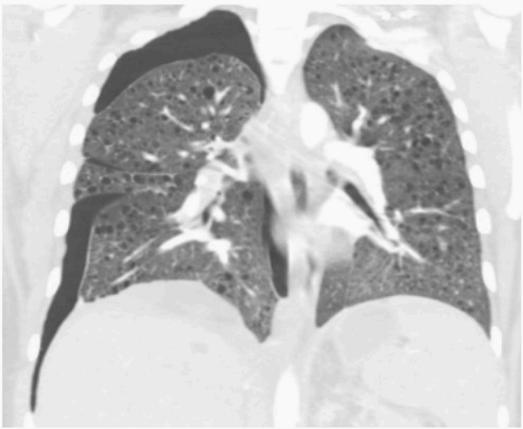

胸片显示右侧气胸,伴少量至中度积液(图1)。CT显示右侧大量气胸和同侧胸腔积液

图2 胸部冠状位CT显示右侧气胸伴双侧弥漫性囊肿和右侧少量胸腔积液